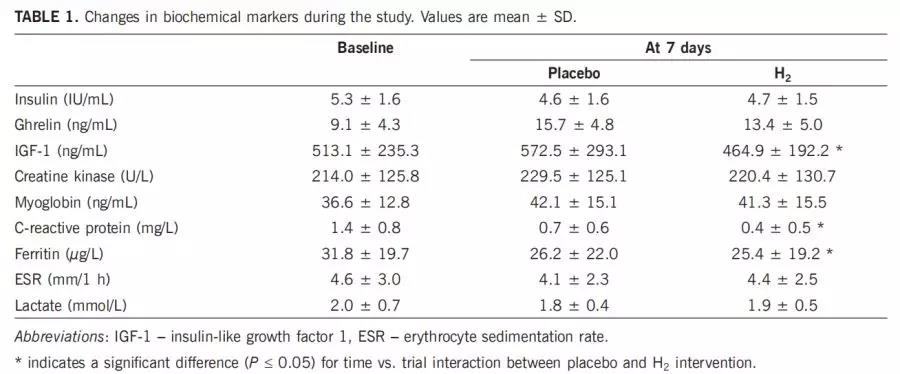

该试验已在ClinicalTrials.gov(IDNCT03846141)上进行了注册。随访期间,与吸入空气相比,每天呼吸4%的氢气20分钟可导致峰值运行速度增加(高达4.2%)。吸氢导致血清胰岛素样生长因子1(IGF-1)显着下降48.2 ng / mL(95%置信区间[CI]:从-186.7降至89.3)(P <0.05),安慰剂干预后IGF-1水平升高59.3 ng / mL(95%CI;从-110.7增至229.5)(P <0.05)。在健康的男性和女性中,吸入氢似乎显示出产生增强机能的特性。应进一步评估气态氢气在运动环境中的功效和安全性。

表1.研究过程中生化标志物的变化。值是平均值±SD。